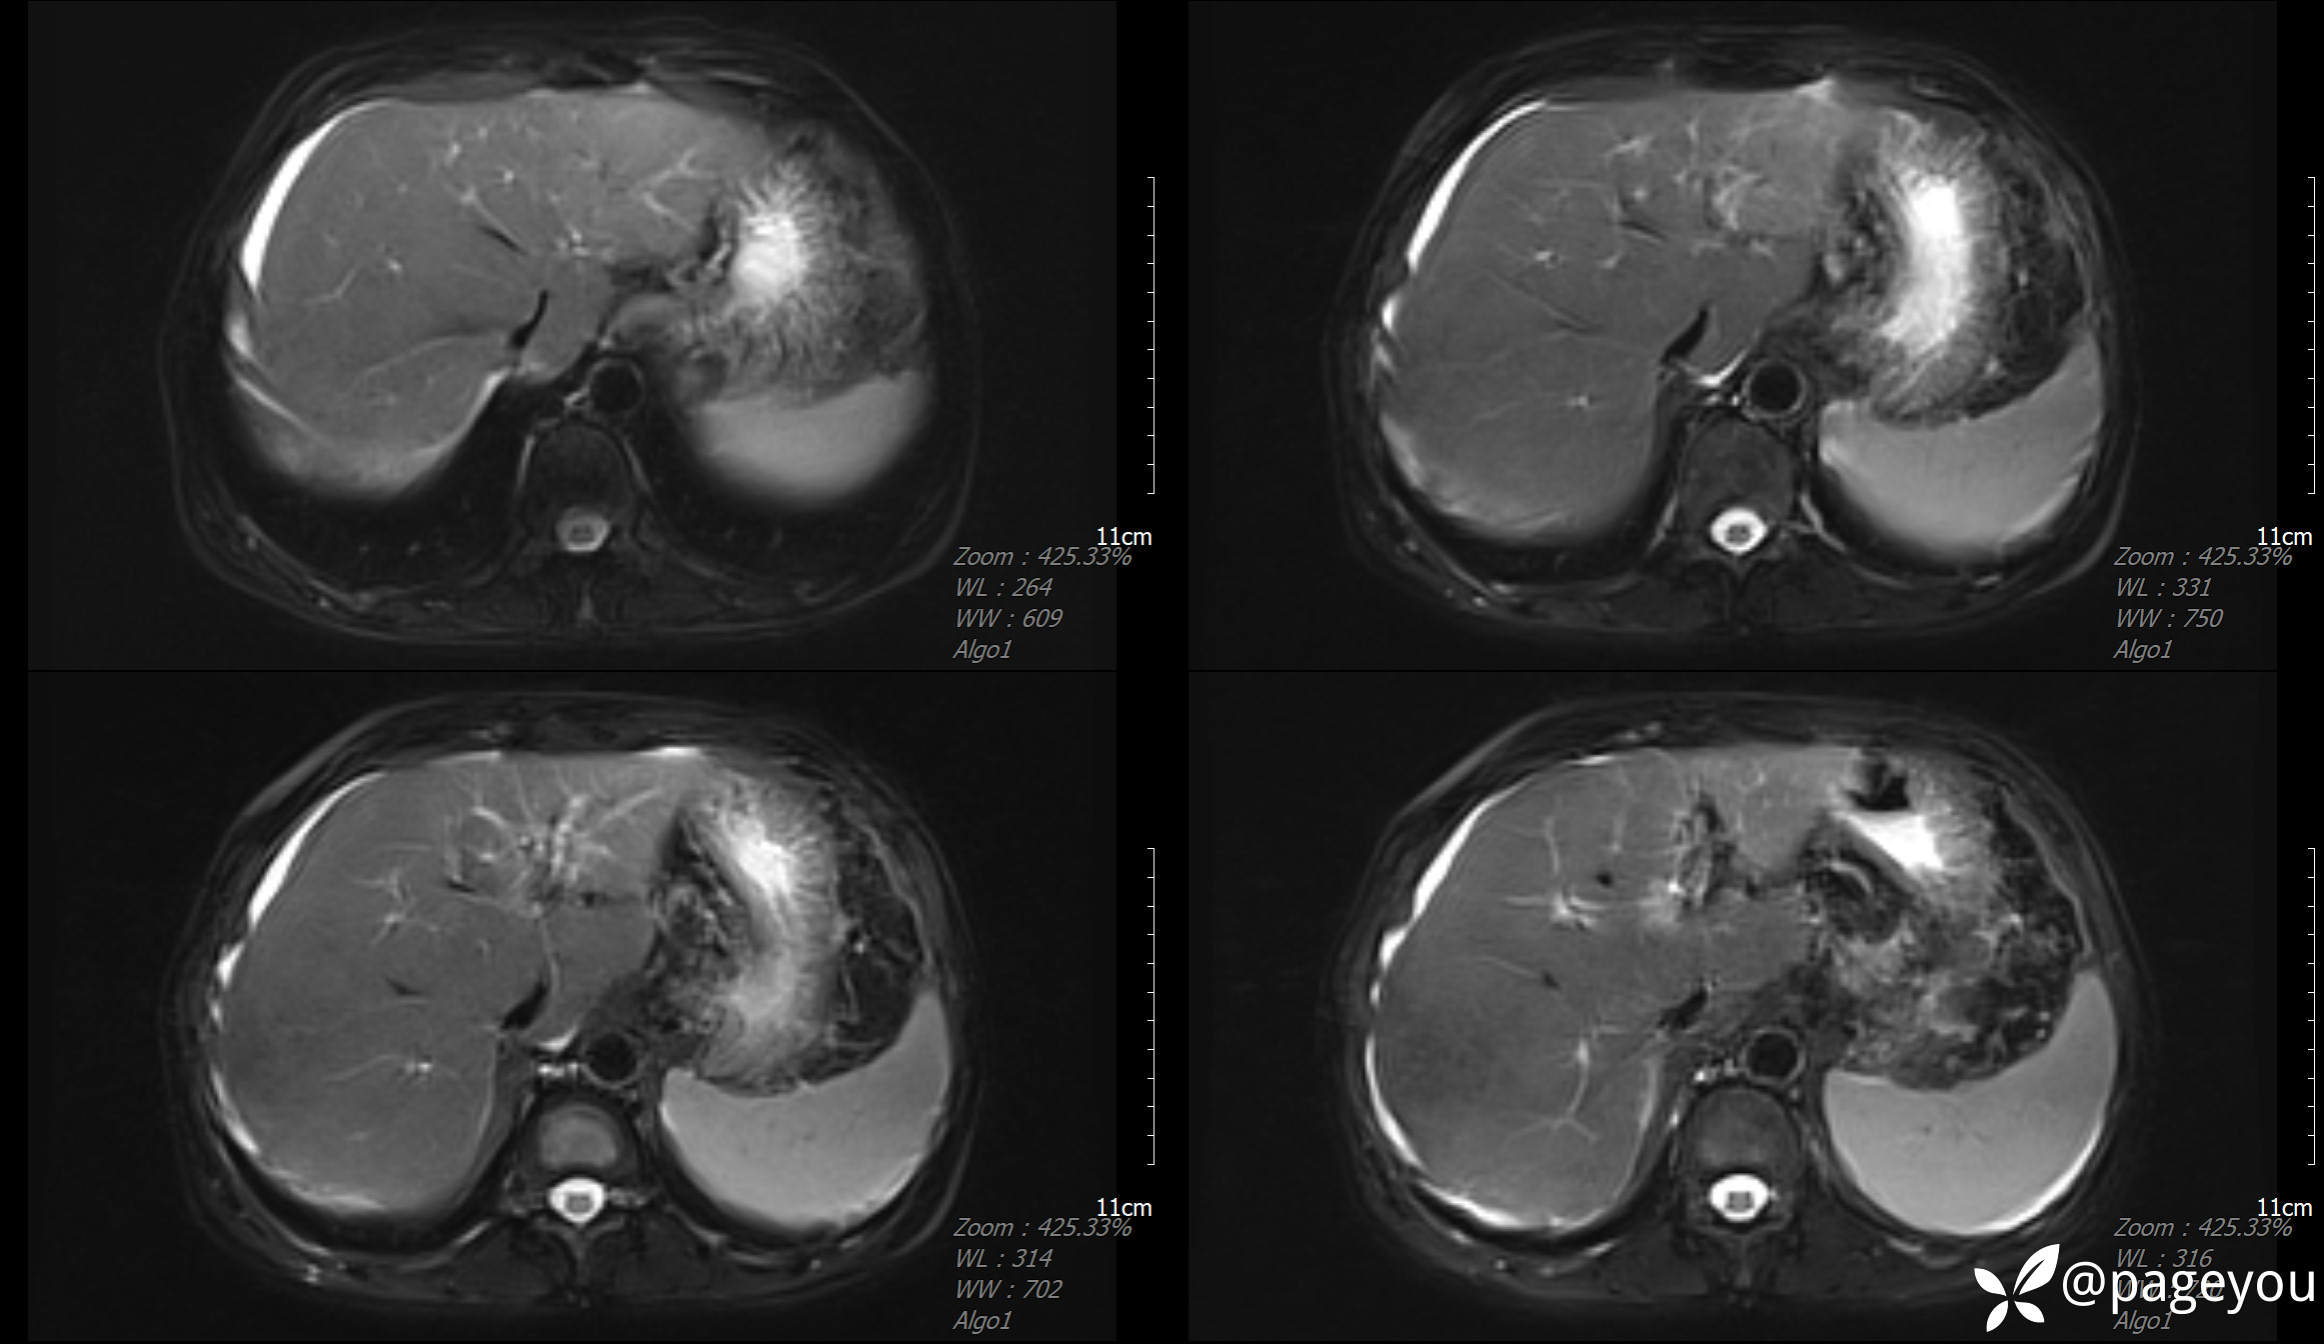

MRI检查: